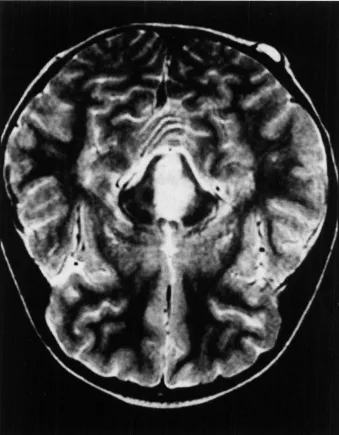

神经节神经胶质瘤(WHO I级)是最常见的致癫痫性肿瘤,尽管它仅占所有脑肿瘤的1%至4%。它往往发生于具有长期药物难治性癫痫病史的儿童和年轻人中。复杂部分性发作最为常见。尽管神经节神经胶质瘤倾向于出现在颞叶,但它可发生在神经轴的任何部位,包括颈髓连接处、松果体区和鞍上区域。颞叶外的位置与组织学异型性和间变性相关(间变性神经节神经胶质瘤;手术是这些肿瘤的主要治疗手段[见图3])。虽然有报道称存在恶性转化可能,但其通常是良性的。幕上神经节神经胶质瘤通常可以实现手术全切,因此是可治愈的,并为约80%的患者带来了Engel I级(无癫痫发作)的结局。为了进一步改善癫痫发作的控制,建议进行脑病灶切除联合邻近颞叶新皮质切除术。实现肿瘤全切的主要障碍是肿瘤的中线位置(如脑干),其他限制因素包括肿瘤边界不清、靠近重要功能皮层以及浸润了关键结构。

图3。一名11岁患儿,右颞部肿瘤表现为多发囊肿并伴有明显强化的实性瘤体部分。术前与术后轴位T1加权磁共振成像对比,提示肿瘤被完全切除,最终病理诊断为神经节神经胶质瘤。